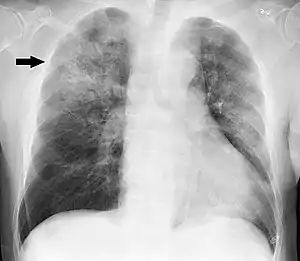

![]() | |

| Chest X-ray of a pneumonia caused by influenza and Haemophilus influenzae, with patchy consolidations, mainly in the right upper lobe (arrow) | |

X-ray presentations of pneumonia may be classified as lobar pneumonia, bronchopneumonia, lobular pneumonia, and interstitial pneumonia.[73] Bacterial, community-acquired pneumonia classically show lung consolidation of one lung segmental lobe, which is known as lobar pneumonia.[41] However, findings may vary, and other patterns are common in other types of pneumonia.[41] Aspiration pneumonia may present with bilateral opacities primarily in the bases of the lungs and on the right side.[41] Radiographs of viral pneumonia may appear normal, appear hyper-inflated, have bilateral patchy areas, or present similar to bacterial pneumonia with lobar consolidation.[41] Radiologic findings may not be present in the early stages of the disease, especially in the presence of dehydration, or may be difficult to interpret in the obese or those with a history of lung disease.[24] Complications such as pleural effusion may also be found on chest radiographs. Laterolateral chest radiographs can increase the diagnostic accuracy of lung consolidation and pleural effusion.[40]